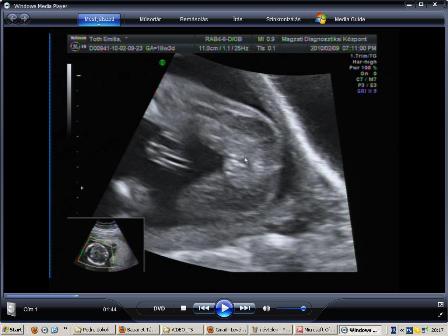

Végre sikerült bescannelnem a múltkori 2D-s UH képet.

Kép

Látszik szemből a pofija...az egyik kezecskéje a mellkasa mellett, míg a másikkal fogja a fülét, és látszik a könyöke. :)